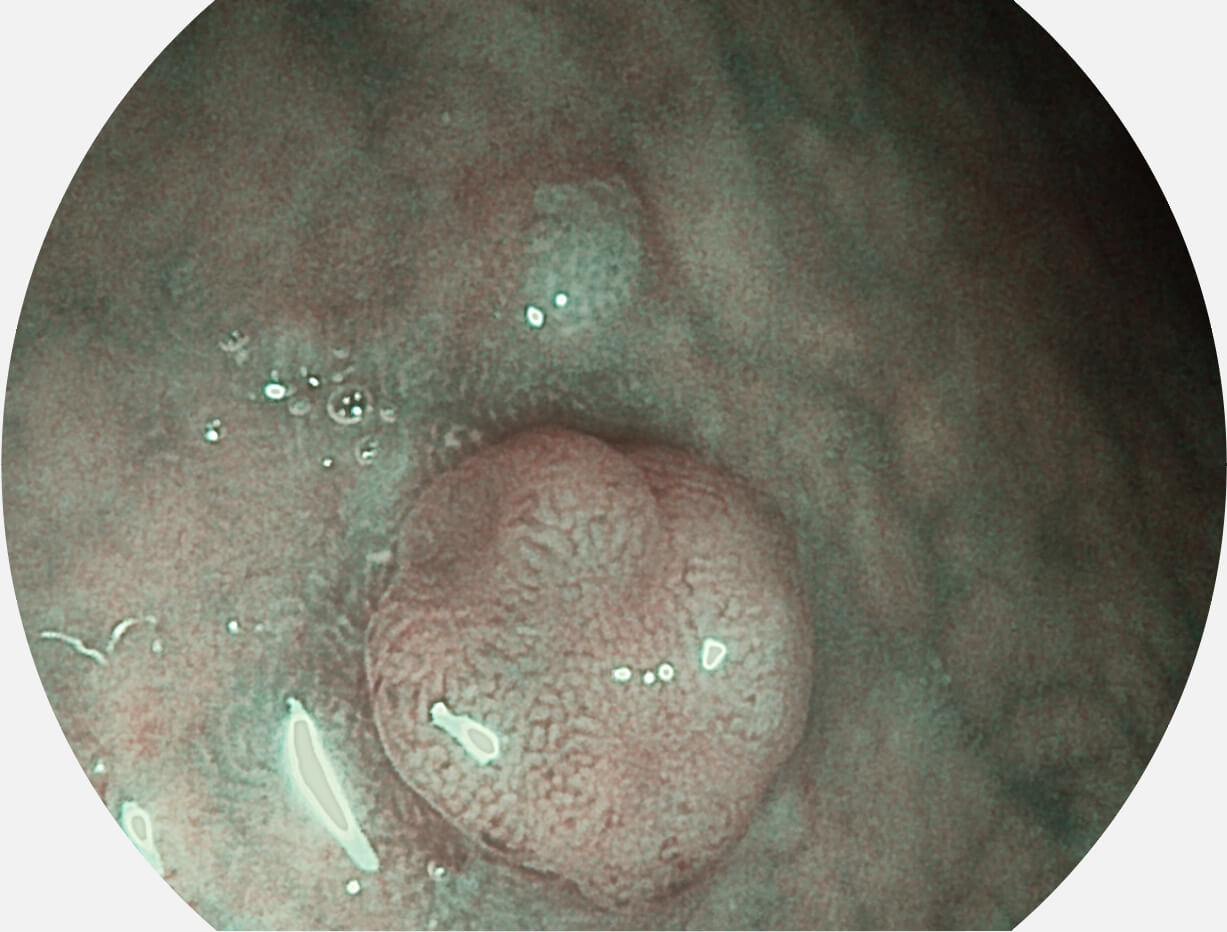

Versatile Intelligent Staining Technology, VIST

强调浅层黏膜结构的同时,保证照明亮度和提升浅层微血管与中层血管颜色对比度,病变边界更清晰。

白光图像

VIST图像

采用光路合束技术,光谱自由度高,实现了更丰富的照明模式,染色模式SFI及VIST,从远景到近景,助力消化道早期疾病诊断。